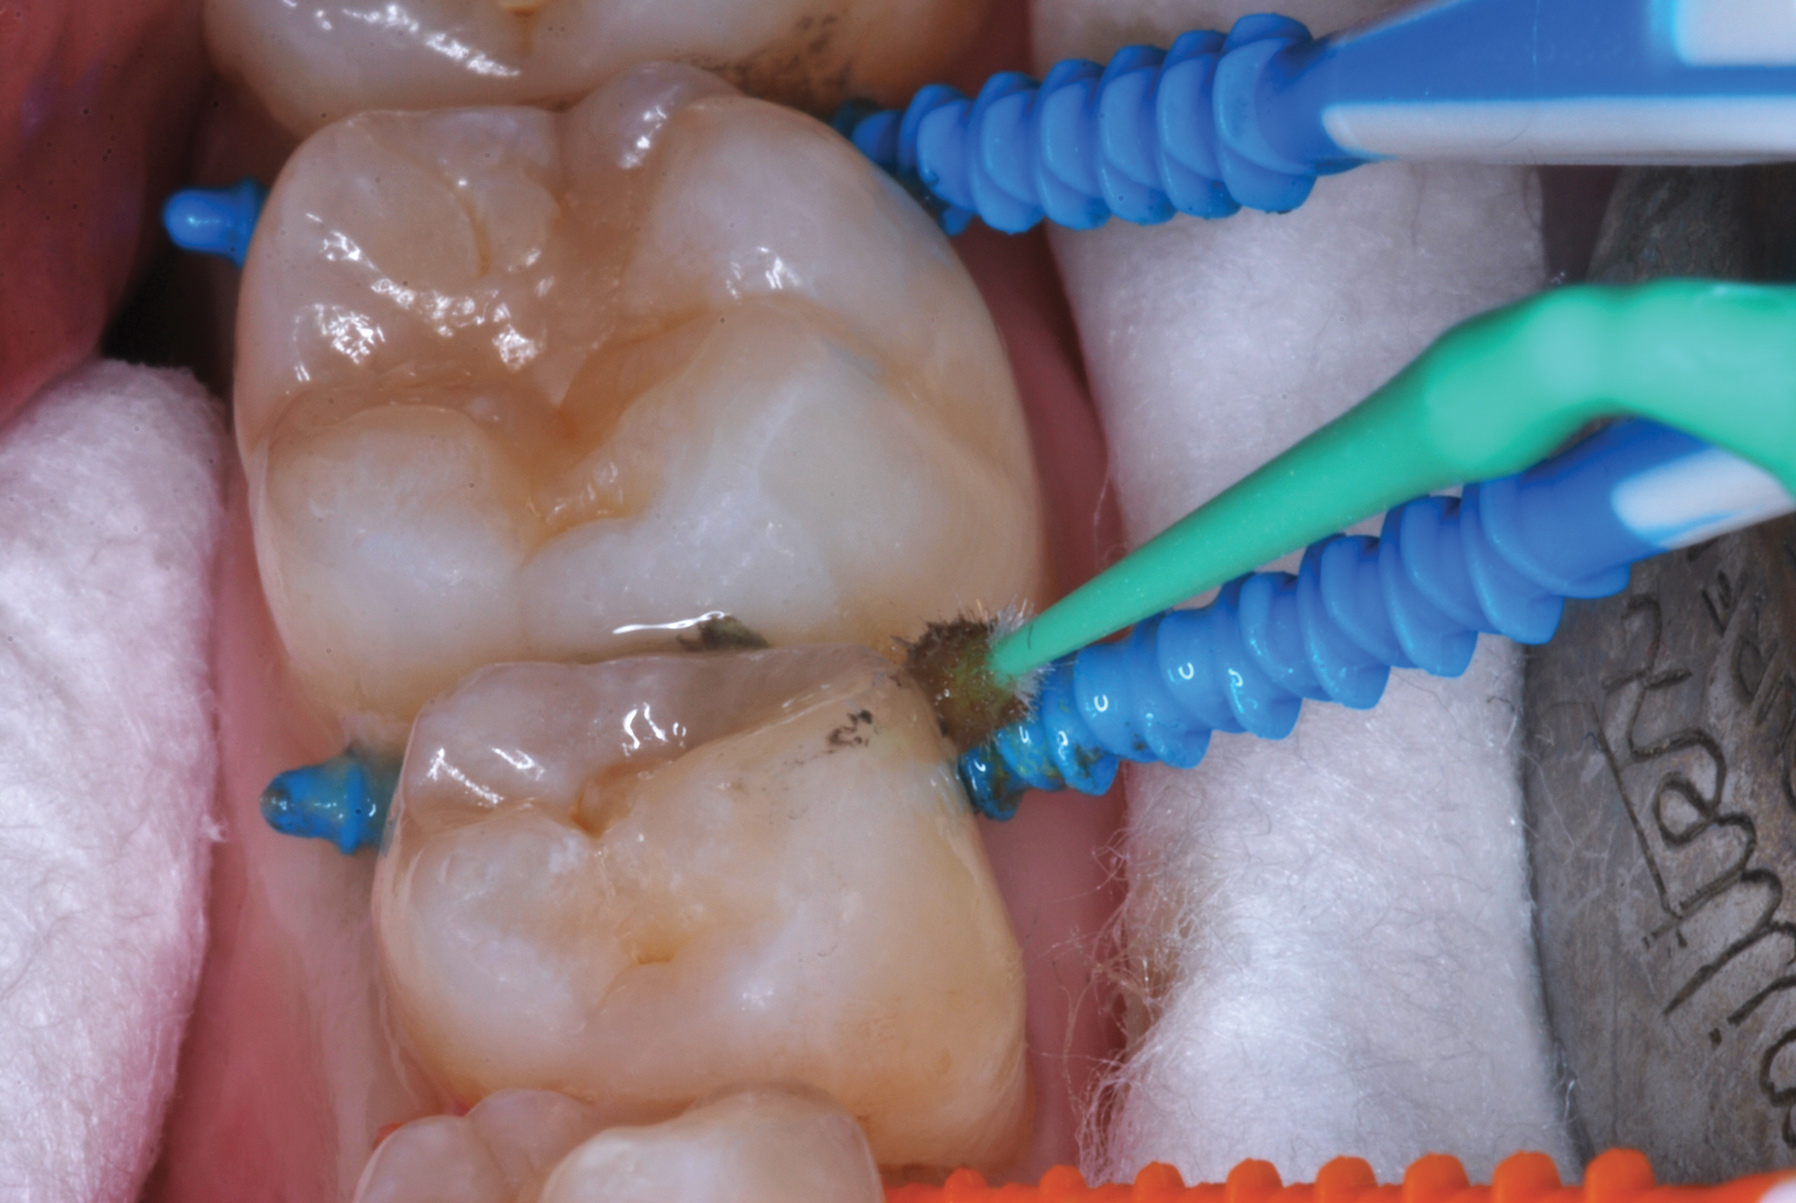

The authors' protocol for insertion of SDF-coated soft dental picks involves isolating the teeth with cotton rolls or other means, flossing the interproximal site to clear food debris and dental plaque, and then inserting a SDF-coated pick (Figure 1 and Figure 2) to saturate the contacting surfaces of the teeth with the fluid. This treatment is painless and requires no anesthetic. The pick should remain in place for at least 60 seconds and can be gently pulled in and out to agitate the fluid for enhanced surface coverage by capillary action. Additional SDF can be wiped on, using a small applicator, above the contact and in the buccal and lingual sluiceways. Excess fluid and any blood elicited may be blotted with a cotton swab. An additional 60-second insertion may be applied in the same way if there is radiographic evidence of a deeper decalcification or caries lesion. With the pick still in place, 5% (or 2.5%) fluoride varnish is painted over the treatment area, and the pick is then withdrawn.

Interproximal insertion of SDF is demonstrated in different patients in Figure 3 through Figure 11. Various diameters and brands of soft dental picks may be used depending on the closeness of the proximal surfaces and ease of insertion; for example, some picks are designed for use in wider spaces between teeth. This protocol also offers versatility. Figure 3, for example, shows the simultaneous use of three thin soft dental picks to saturate proximal surfaces with SDF in a teenaged patient; the treated regions were subsequently covered with fluoride varnish (Figure 4). This patient was initially treated in April 2019 (Figure 5), with an identical re-application 3 months later. As shown in Figure 6, the December 2019 bitewing film revealed good results with the possible exception of the contact regions of the maxillary first and second molars. New SDF application was completed in the December appointment.

Fig 8. Caries prevention with SDF is critical on distal surfaces of primary second molars to avoid caries infection on mesial surfaces of permanent first molars. Note the Class 2 restorations in both primary molars in this 9-year-old patient whose first molar needed occlusal resin-based composite restoration.

Figure 8

Fig 9. Sometimes two picks can be comfortably inserted so that a greater amount of SDF solution may be used for maximum fluid saturation.

Figure 9